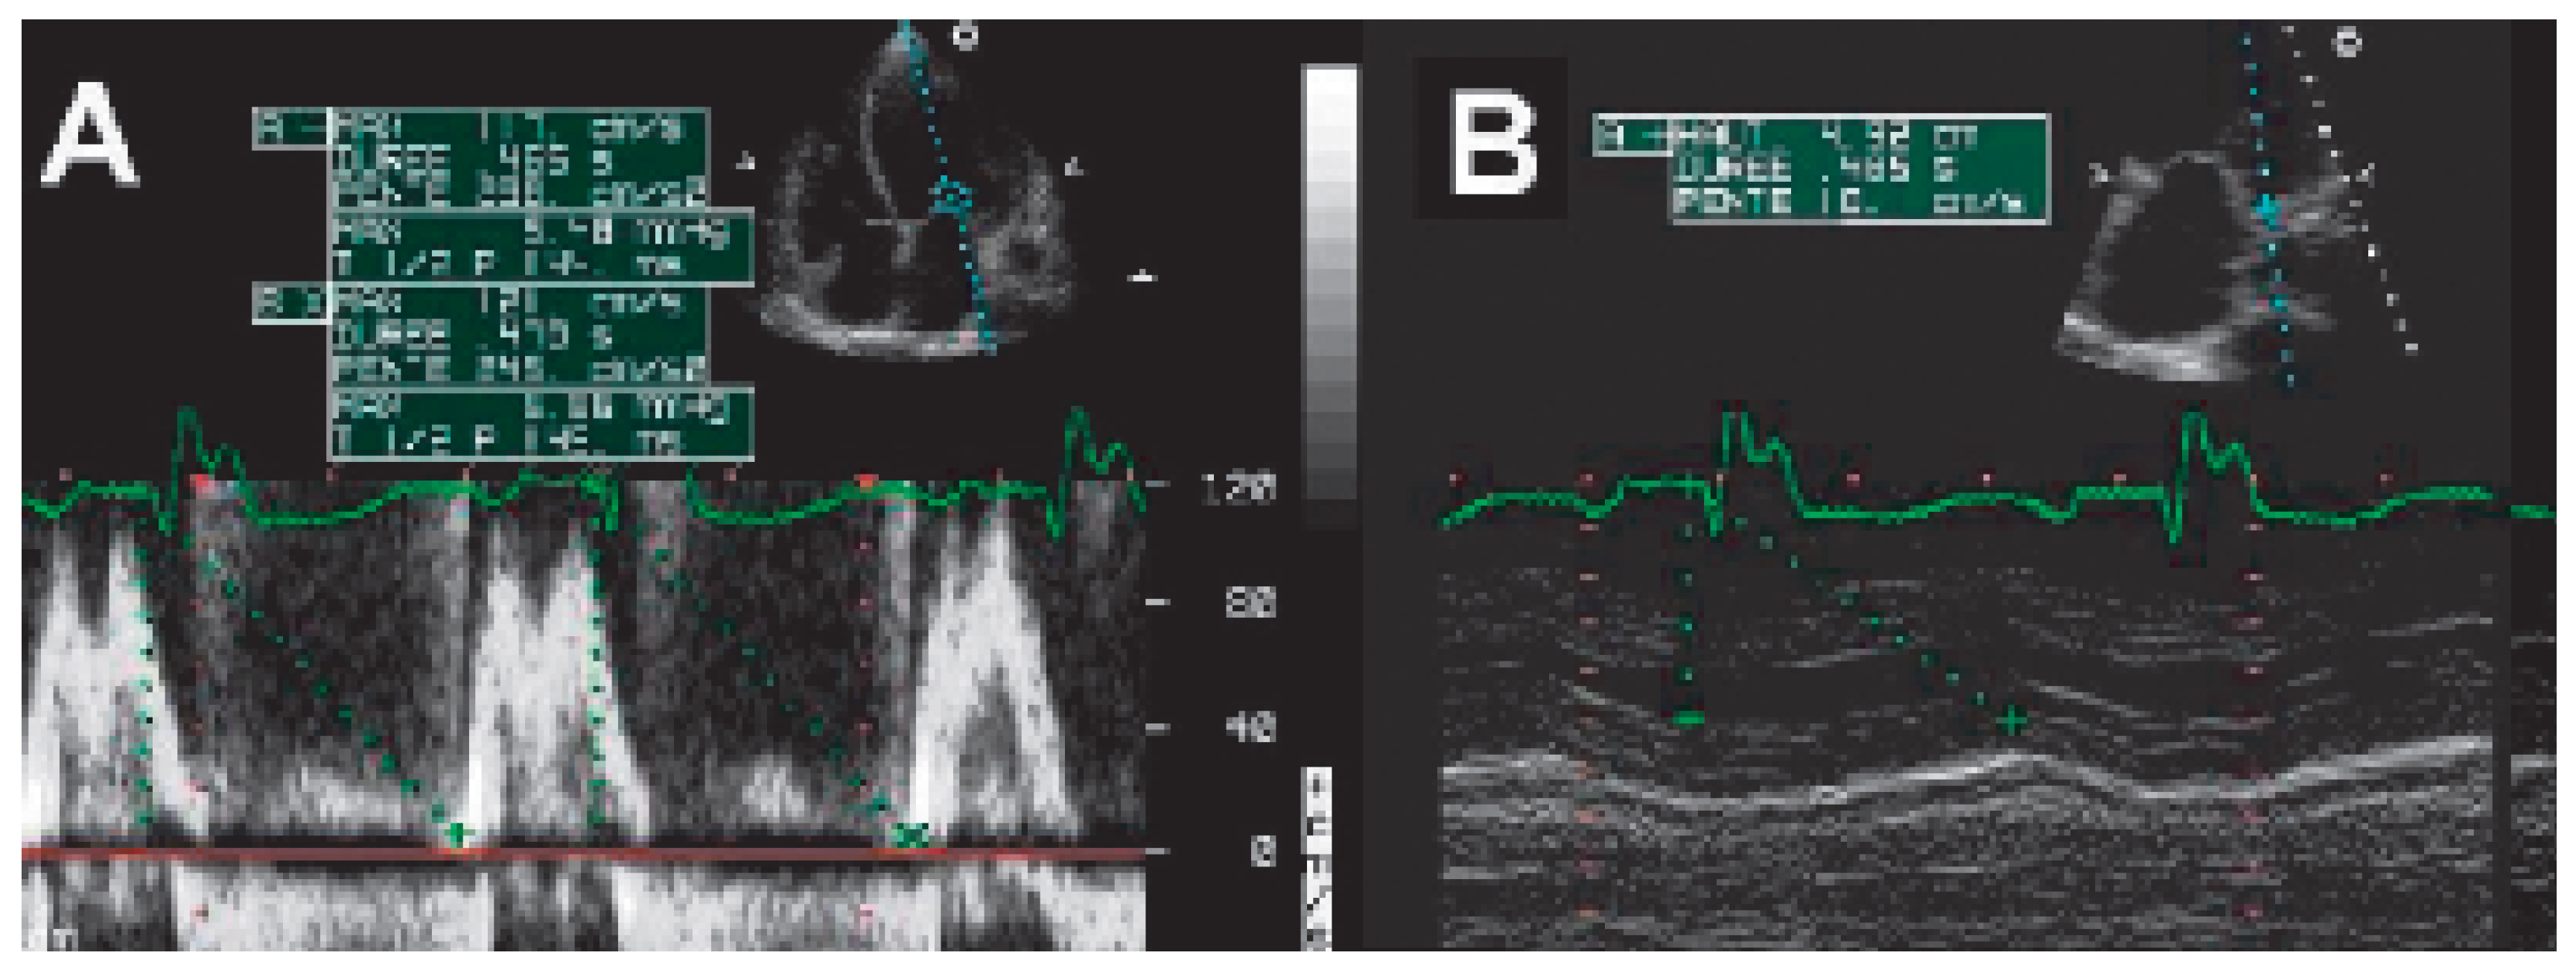

M-mode echocardiography

AV interval optimisation